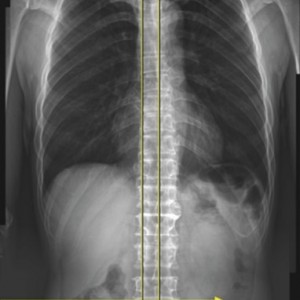

성인의 80%~90%에서 골반 부정렬이 발견되었으며,

그 중 3분의 1은 무증상, 3분의 2는 요통, 골반통 등의 증상을 호소한다.

Wolf Schamberger - The Malalignment Syndrome 中